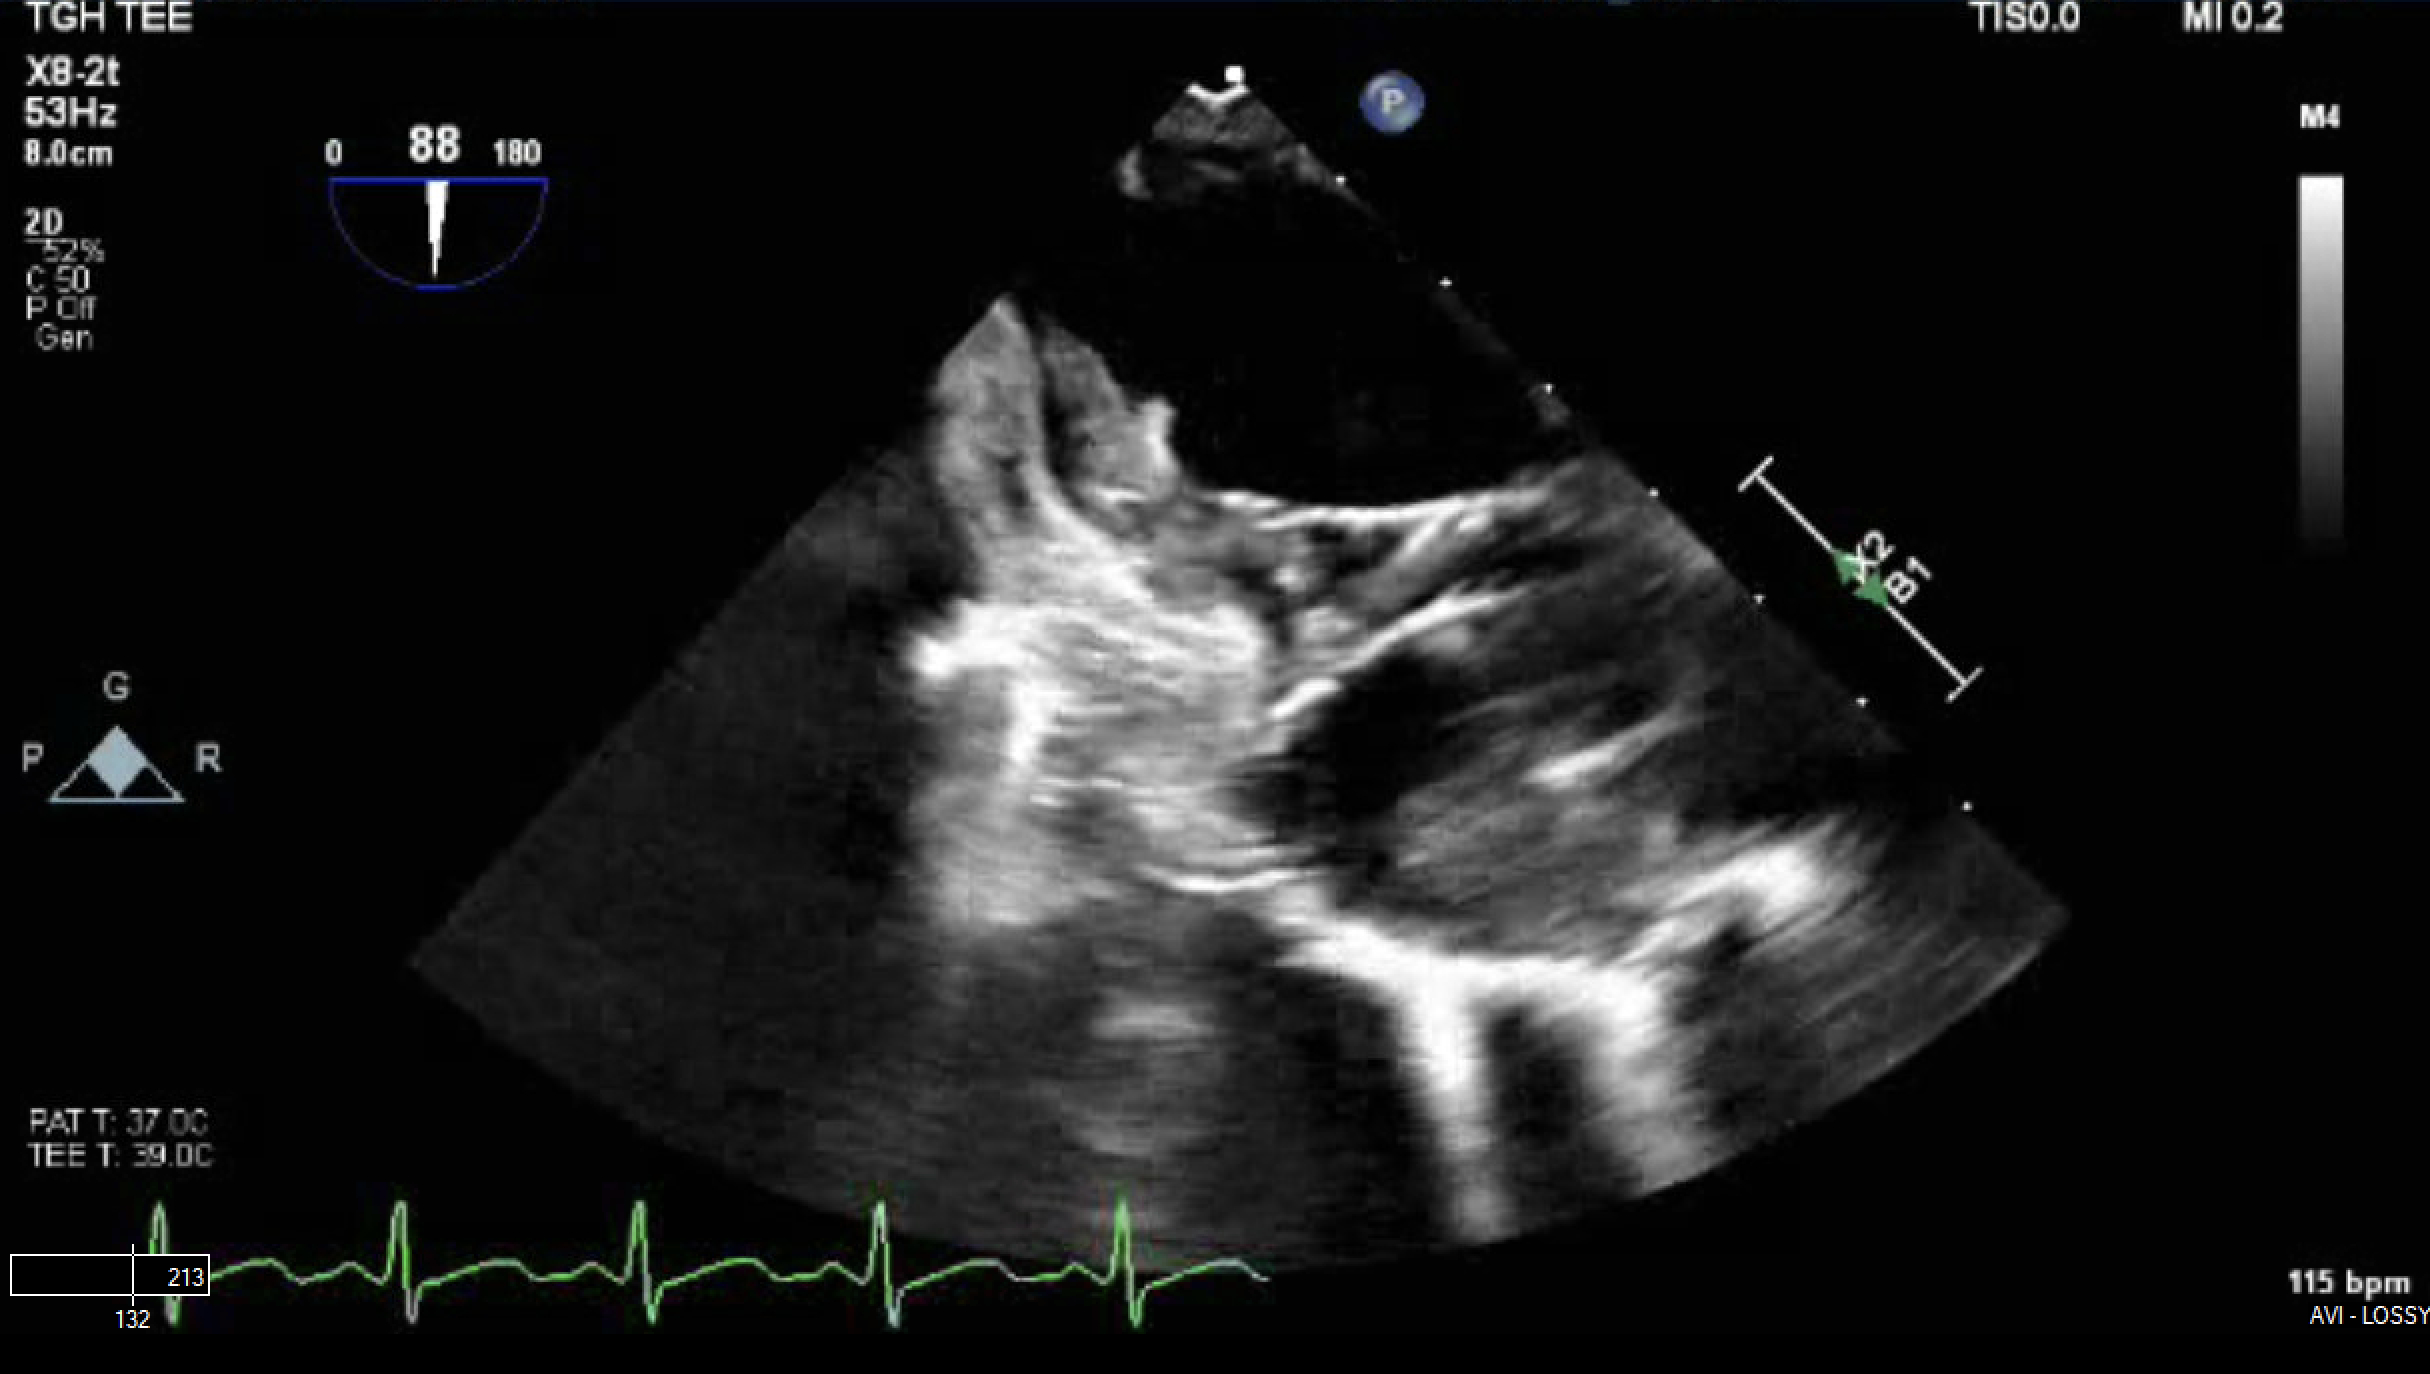

A 27-year-old female with recurrent fevers, arthralgias, an evanescent rash, and hyperferritinemia (10,661 ng/mL) was diagnosed with AOSD following an initial presentation of macrophage activation syndrome (MAS). She improved with anakinra and corticosteroids. Months later, she was readmitted with fever and hypotension requiring vasopressors. Infectious workup was negative, and recurrent MAS was diagnosed. Transthoracic echocardiography revealed severe PH and a mobile right atrial thrombus, initially suspected to be central-line associated; the central line was subsequently removed. She responded to intensified immunosuppressive therapy. Days later, she developed headaches and seizures. Brain MRI showed posterior vasogenic edema concerning for posterior reversible encephalopathy syndrome (PRES), likely related to immunosuppression. Her condition rapidly deteriorated with severe headache and bilateral fixedly dilated pupils. Imaging revealed bilateral cerebellar infarctions with hemorrhagic conversion and tonsillar herniation, prompting emergent suboccipital craniectomy and external ventricular drain placement. A follow-up transesophageal echocardiogram identified two large (>2 cm) right atrial thrombi, one highly mobile, indicating persistent thrombosis despite line removal. Agitated saline contrast confirmed a patent foramen ovale with right-to-left shunting.

Given recent intracranial hemorrhage, anticoagulation was contraindicated. Due to the risk of embolization and obstruction, she underwent successful percutaneous AngioVac-assisted thrombectomy. She was also treated with emapalumab targeting interferon-γ to control systemic hyperinflammation.